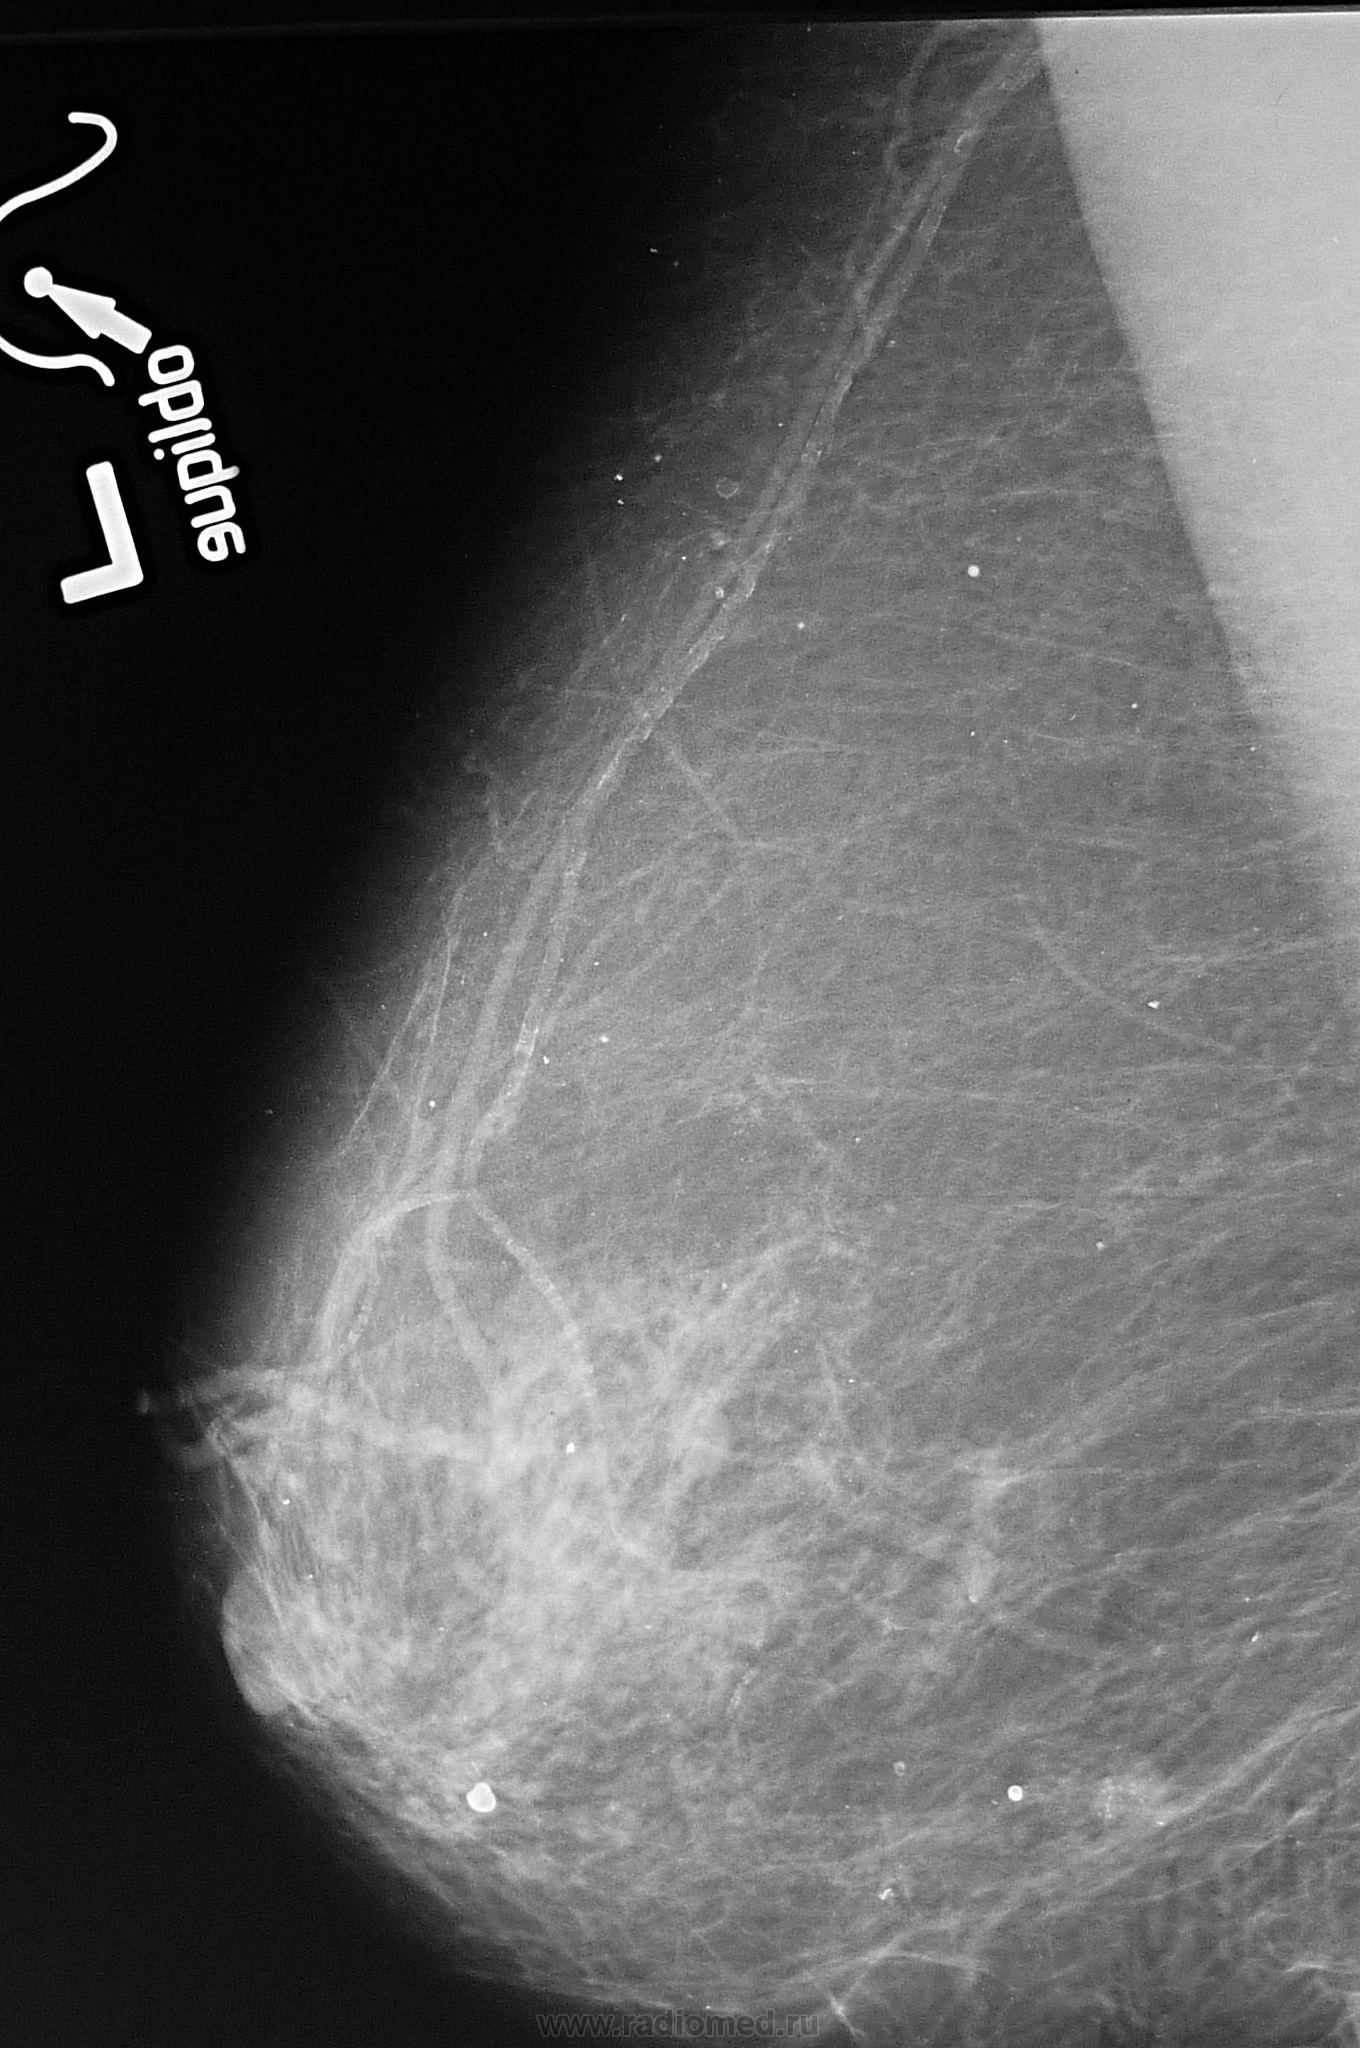

Для снимков с увеличением на вашем маммографе есть приставка и маленький тубус,  железа кладется на столик, режим выбирается вручную, я часто использую 23-125, или 22-100 в зависимости от размеров желзы, очень хорошо видны контуры образования, микрокальцинаты.